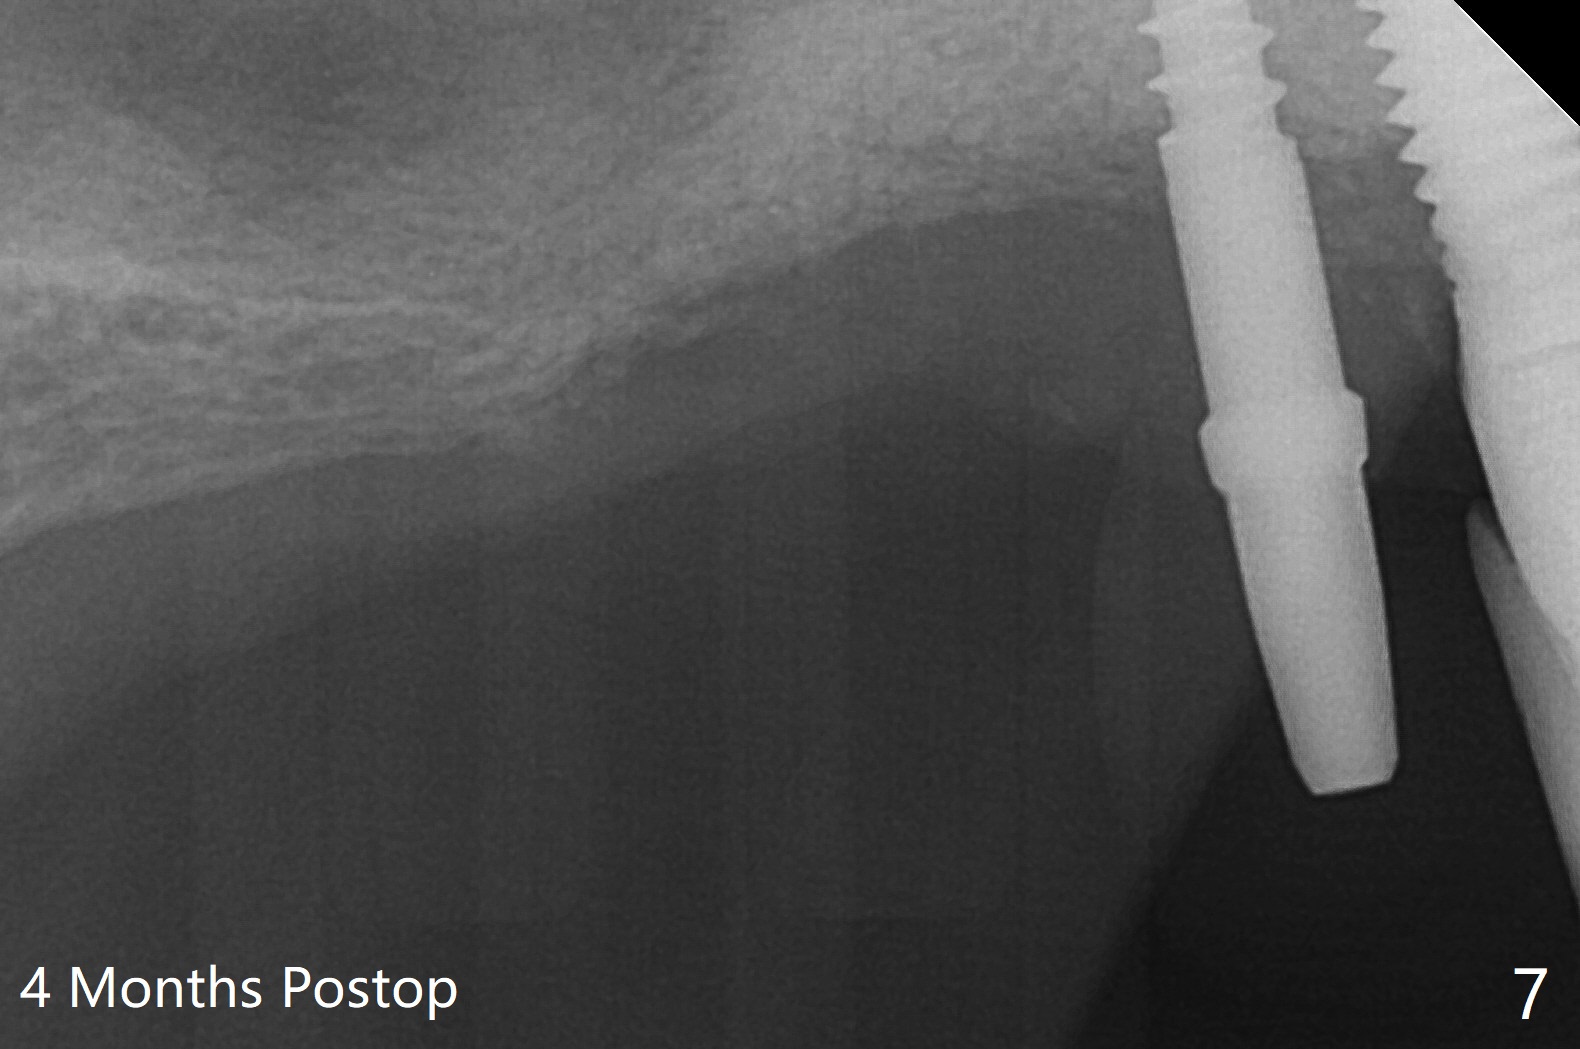

术前检查发现右上6颊侧牙龈沟有脓性分泌物(图一),翻瓣显示骨质吸收(图二),曾经植骨三次,只好去骨,取出植体,远中颊侧轻度上颌窦穿孔(图三:>),塞入小块PRF膜后,患处放置粘性骨粉,覆盖两块PRF膜和一片GEM Cap(9-12月吸收膜),三者近中一端有一个洞,挂在5基台上固定。术后即刻根尖片显示骨粉充填穿孔(图四:>),6缺失区以及5远中(*)。术后第二天牙周敷料脱落,术后16天病人回来,要求剪除缝线,伤口尚未关闭,下面黄色骨粉好像挺牢靠;为了减少继续骨粉丧失,使用树脂敷料(图五)。术后四周敷料稳定,牙龈健康,但是不放心下面伤口愈合,暂时没有撤去敷料。术后四个月骨质高度不足(图六至八),上颌窦膜薄,提升不容易,可放置5x7.3毫米植体(IBS),PRF。Return to No Caries 4 Placement 种植杂谈 Xin Wei, DDS, PhD, MS 1st edition 01/26/2021, last revision 07/30/2021